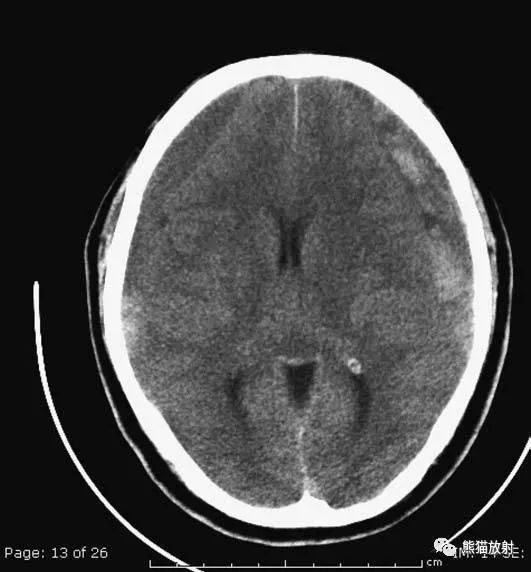

颅脑CT常用的三个窗(图A-C):图A:骨窗(the bone window)。

图B:脑窗(the brain window)。

图C:血窗(the blood window)。

图A:骨窗;主要用于明确骨折、窦腔病变、颅内积气。

图B:脑窗;可清晰显示灰白质,可发现中风的早期征象或其他导致脑水肿等表现的病变。

图C:血窗;更利于显示硬膜下或颅内出血。本例表现:骨窗示:右顶骨骨折;三个窗均示:软组织水肿并皮下积气;血窗:少量硬膜下血肿。